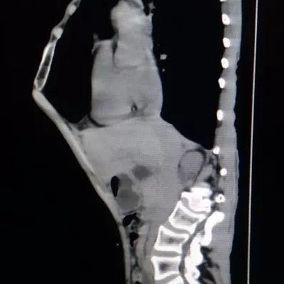

After a preoperative examination, it is observed that the patient's anterior chest wall protruded severely, reaching its peak at the xiphoid process, which presented as a 90-degree angle when viewed from the side. The heart is displaced to the right chest cavity, and the torso is severely deformed, characterized by a broad chest and a noticeably narrowed waist and abdominal area. The narrowing is most pronounced above the pelvis. Moreover, a chest CT scan reveals two large cysts located between the heart and the anterior chest wall in the lower lobe of the left lung, measuring 7x8 cm and 9x10 cm respectively.